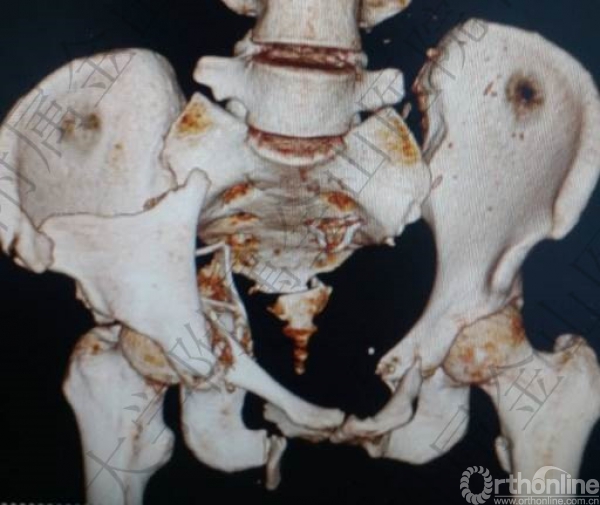

头胸腹CT未见明显实质脏器损伤,骨盆多发骨折:右侧髋臼骨折(双柱)。

骨盆骨折(C2)

2.骨盆多发骨折:右侧髋臼骨折(双柱)骨盆骨折(C2)(失血最主要原因);